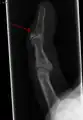

Description de cette image, également commentée ci-après

Majeur en maillet. La dernière phalange est fléchie alors que les autres doigts sont droits.